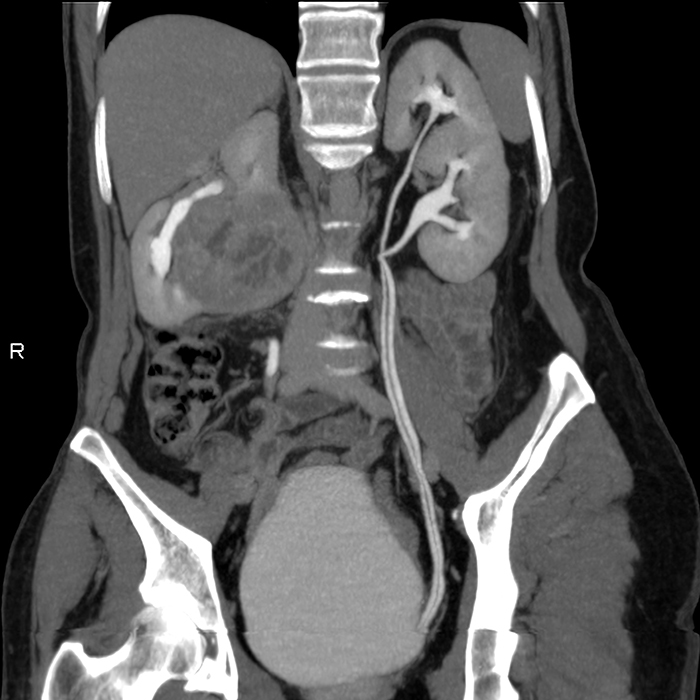

Изображения КТ конкрементов мочевого пузыря